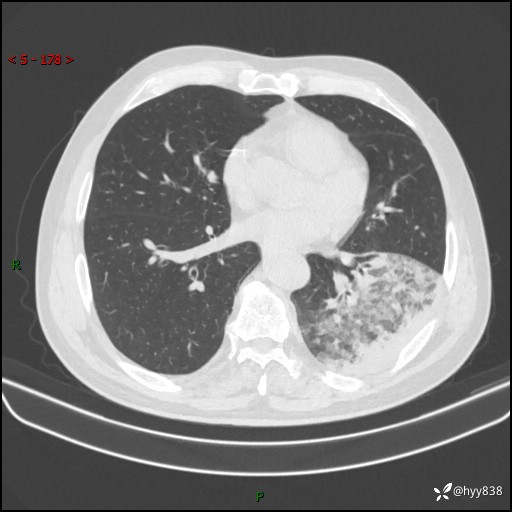

59岁/男,发热伴咳嗽3天。白班偶遇,“大叶性肺炎”,病原体挑战---结果公布~

【患者信息】:59岁/男

【主诉】:发热伴咳嗽3天

【现病史及既往史】:患者3天前无明显诱因出现发热,体温最高达38.6℃,伴有咳嗽,干咳为主,感乏力、肌肉酸痛,无明显头晕头痛、鼻塞、流涕、呼吸困难、胸痛、恶心呕吐、腹痛腹泻、尿频尿急等不适,于当地诊所输液治疗3天感症状无好转,仍有间断发热、咳嗽,现为求进一步诊治,于我院门诊就诊,门诊以“发热待查”收入我科进一步诊治。 患者自发病以来,精神、饮食、睡眠欠佳,大小便正常,体力、体重无明显变化。

【检查】:胸部CT平扫